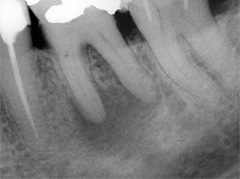

Der umfangreiche kariöse Defekt steuerte sehr bald hin auf die komplette Entfernung des Zahninnen­gewebes mit anschliessendem medikamentösen Wiederverschluss. Aufbissempfindlichkeit am Folgetermin ist immer Aufforderung zur erneuten Intensivsuche nach weiteren Kanälen, die hier einen 4. Ast zum Vorschein brachte. Nach 2 ausgelassenen Terminen

waren vorrangig Wiederherstellung von desinfizierender Einlage und provisorischer Füllung angezeigt. Eine weitere Woche später wurde in allen Kanälen das Medikament durch die endgültige Verschlussmasse ersetzt, worauf Zahn 36 mit 12-tägiger Verzögerung erneut zu rebellieren begann. Das hiess aus den hinteren Wurzeln Füllmaterial wieder raus und

Einlage erneut rein. Als es dann 4 Wochen später bei der hinteren Wur­zel aussen anzuschwellen begann und ein Medikamentenwechsel ohne Wir­kung blieb, wurden die hinteren Ka­näle abgefüllt und auch in gleicher Sitzung das überstopfte Material (Bild 1) mittels Resektion (Bild 2) von aussen entfernt.

Die ersten beiden Aufnahmen sind aus dem Jahr 1999, die 3. von 2006